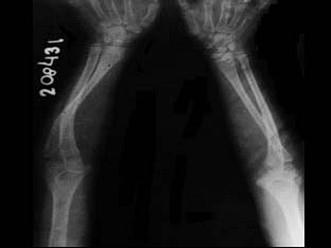

问题 女,2岁,有蓝色巩膜、听力障碍,四肢畸形等,请结合所提供图像,选择最佳选项 ( )

选项 A、呆小病 B、成骨不全 C、维生素C缺乏病 D、软骨发育不全 E、维生素D缺乏病

答案 B